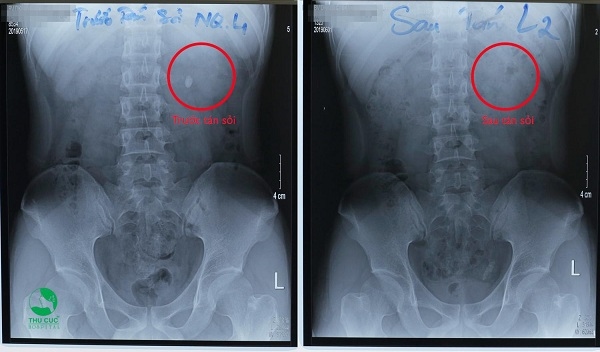

Kết quả một ca tán sỏi ngoài cơ thể không cần mổ.

“Tại Bệnh viện ĐKQT Thu Cúc, từ khi bắt đầu triển khai đến nay, có hàng ngàn bệnh nhân tìm đến để thoát sỏi không cần mổ”, bác sĩ CKII Phạm Huy Huyên (Phó Giám đốc, Trưởng khoa Ngoại ) chia sẻ. Tán sỏi ngoài cơ thể ở Thu Cúc cũng được giới thiệu trên sóng truyền hình quốc gia, thu hút sự quan tâm của người dân không chỉ ở khu vực Hà Nội mà còn từ nhiều tỉnh thành trên khắp cả nước. Anh H. Đ. Mạnh (30 tuổi, Thanh Hóa) vừa xử lý sạch viên sỏi thận 1cm nhờ tán sỏi ngoài cơ thể phấn khởi cho biết: “Mình cũng đi khám ở nhiều nơi rồi nhưng nghe phải mổ thì…về luôn. Đến Thu Cúc được tư vấn tán sỏi ngoài cơ thể không cần mổ thì quyết định điều trị ngay.”